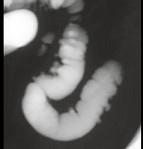

男,52岁,习惯性便秘2年余,结合图像,应诊断为 ( )A、结肠息肉病B、结肠转移瘤C、结肠憩室病D、假膜性结肠炎E、溃疡性结肠炎

问题 男,52岁,习惯性便秘2年余,结合图像,应诊断为 ( )

选项 A、结肠息肉病 B、结肠转移瘤 C、结肠憩室病 D、假膜性结肠炎 E、溃疡性结肠炎

答案 C